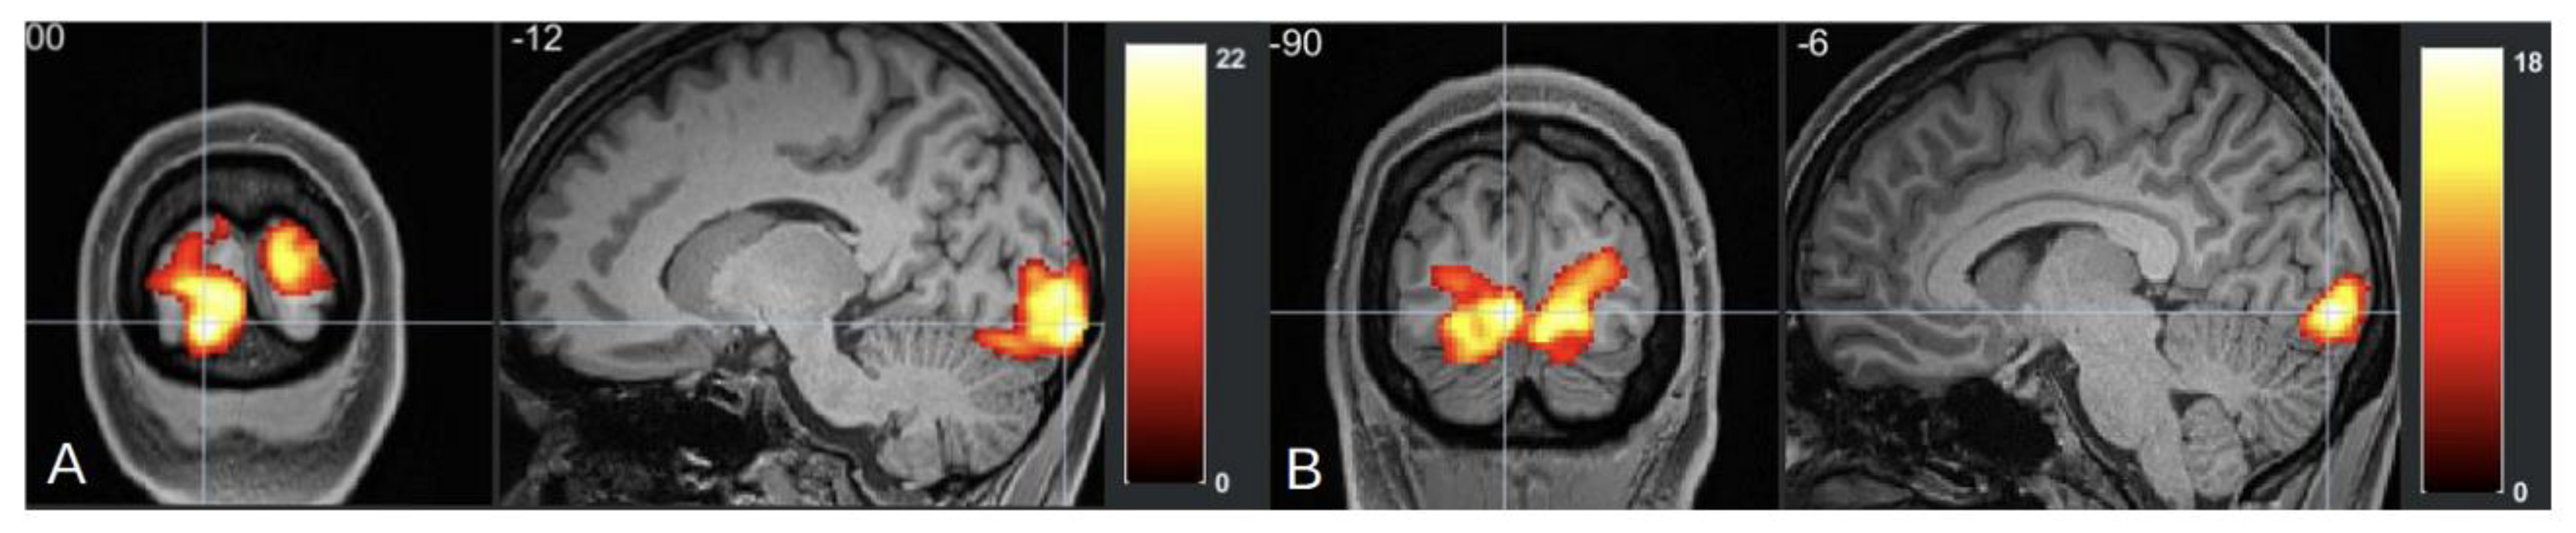

Functional MRI (fMRI) studies of migraine with aura (MA) have identified distinct neural alterations, particularly in resting-state functional connectivity (rs-FC). Increased rs-FC is observed in regions such as the occipital cortex, sensorimotor networks, and visual areas like the lingual gyrus, which play a critical role during both ictal and interictal phases of MA [97,98], [Figure 3 and Figure 4]. Altered connectivity is also found in the thalamus, insula, and cingulate cortex, suggesting the involvement of key pain-processing networks [99]. Furthermore, differences in rs-FC between MA and migraine without aura (MwoA) point to potential biomarkers distinguishing these subtypes [100]. These findings support the notion that distinct neural circuits may underlie the different clinical presentations of migraine, offering new insights into the pathophysiology of the disorder. In tension-type headache (TTH), fMRI studies highlight distinct neural changes that may offer insight into the underlying mechanisms of the condition. Increased fractional amplitude of low-frequency fluctuations (fALFF) is observed in the right posterior and anterior insula in episodic TTH patients compared to healthy controls, while reduced fALFF is found in the posterior cingulate cortex [101]. ReHo analysis reveals increased activity in the right medial superior frontal gyrus [102], though other studies report decreased ReHo in regions such as the bilateral caudate nucleus and frontal gyri [103]. These findings suggest a disrupted balance of activity across key pain and sensory processing regions, providing a better understanding of TTH’s neural basis and potential therapeutic targets. In trigeminal autonomic cephalalgia (TAC), including cluster headache (CH), fMRI studies have documented altered functional connectivity and brain activation patterns. In CH, increased rs-FC is noted between the hypothalamus and regions such as the pregenual anterior cingulate cortex, visual cortex, thalamus, and right insula [104]. Decreased FC is observed in the right frontal pole and right amygdala in chronic CH patients [105]. These altered connectivity patterns suggest that disruptions in both the sensory and emotional processing circuits contribute to the intensity of pain in CH. Additionally, TAC subtypes like short-lasting unilateral neuralgiform headache attacks with conjunctival injection and tearing (SUNCT) exhibit activation in the posterior hypothalamus, brainstem, and frontal cortices during attacks [106,107,108]. This indicates a significant involvement of the hypothalamus and brainstem in the pathophysiology of TAC. In the case of other primary headaches, such as new daily persistent headache (NDPH), fMRI studies have shown abnormal functional connectivity in brain regions involved in emotion and pain regulation [109]. These abnormalities suggest that NDPH may involve disrupted integration between pain processing and emotional regulation networks. Additionally, structural changes, including alterations in cortical area and grey matter volume, have been reported in NDPH patients [110]. These structural findings further emphasize the chronic nature of NDPH and its potential link to persistent alterations in brain structure and function. These findings underscore the complex neural mechanisms underlying these various headache disorders, suggesting that personalized treatment strategies targeting these neural alterations may hold promise for more effective management.

Figure 4. (A) fMRl imaging of occipital cortex of patient with migraine during aura episode, (B) fRl imaging ofoccipital cortex of patient with tension type headaches. In this study, both patients were presented withidentical visual stimuli during the fMRI session.